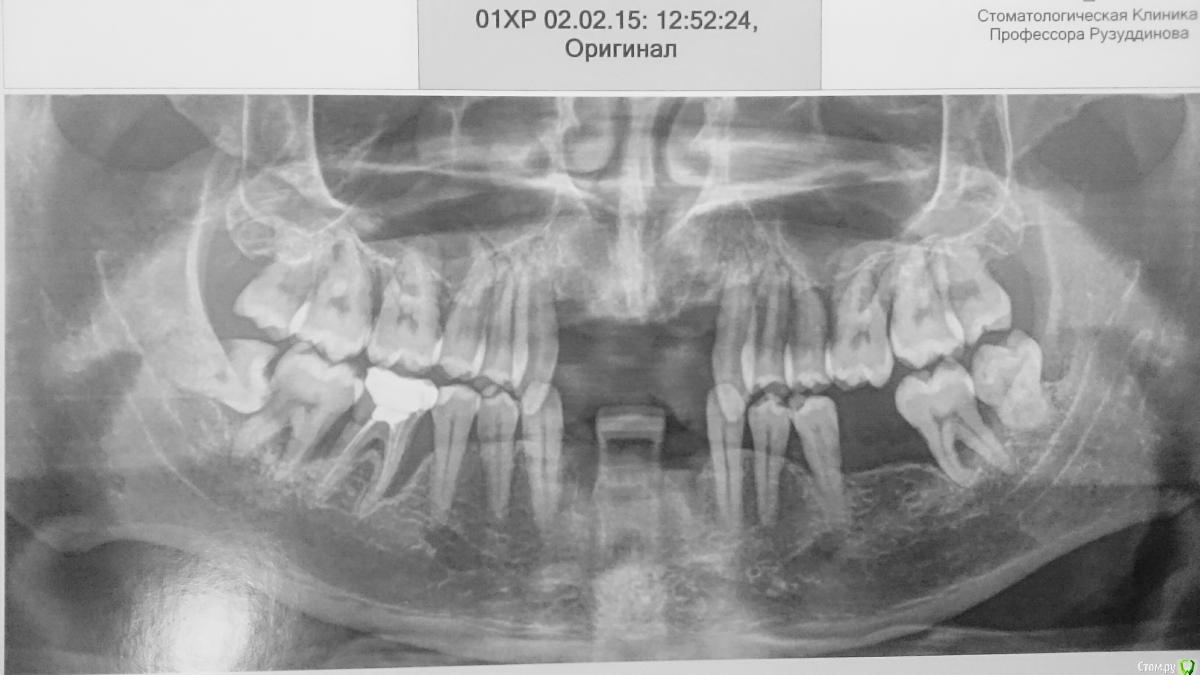

Vla Опубликовано 5 февраля, 2015 Поделиться Опубликовано 5 февраля, 2015 Именно такой диагноз поставил мне стоматолог в одном провинциальном городе Казахстана.У меня запущенный парадонтоз. Зубы практически все подвижные. Пару недель назад мне их подвигали так, что восемь передних ушло. Поехал в Алматы на консультацию. Врач смотрел мне в рот и говорил, что все очень плохо, а я смотрел в его глаза и видел там $$$. Вердикт следующий: удаление всех зубов, синус везде из-за плачевного состояния кости, 15 имплантов и протезирование. За все объявил 15000$. Я не горю желанием ремонтировать зубы в Казахстане, но местные жители утверждают, что цены на стоматологию у них не высокие. Сам Я из Москвы и собираюсь в скором времени вернутьсяУважаемые форумчане у меня к Вам несколько вопросов.1. Реально ли подчиниться в Москве за эту сумму [15000$]?2. Есть ли альтернативный план лечения? 3. И очень бы хотелось попасть к профессионалу, ибо мой случай "интересный". Посоветуйте... Ссылка на комментарий